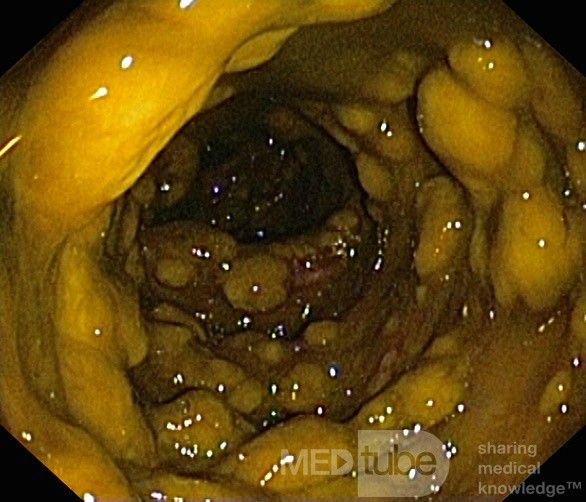

Clostridium difficile is an organism present as normal flora of the gut. Inflammation of the large intestine can occur after antibiotic use secondary to abnormal growth of clostridium difficile. C. difficile releases toxins that causes inflammation and bleeding in large intestine. The major antibiotics associated with pseudomembranous colitis are: - Cephalosporins - Fluroquinolones - Ampicillin - Clindamycin Reference: https://medlineplus.gov/ency/article/000259.htm#:~:text=Pseudomembranous%20colitis%20refers%20to%20swelling,of%20diarrhea%20after%20antibiotic%20use. Image via: https://medtube.net/gastroenterology/medical-pictures/11390-endoscopic-appearance-of-the-pseudomembranous-colitis